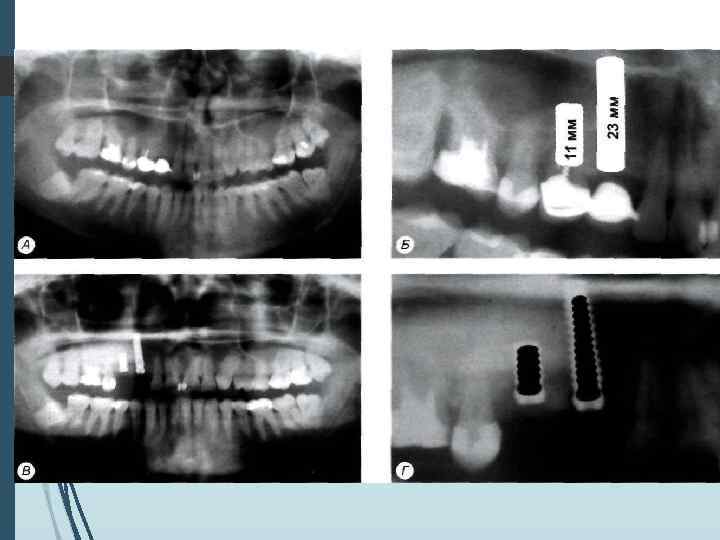

Однако следует учитывать, что даже при правильной укладке и методике ортопантомография даёт искажения реальных размеров челюстей до 10% по вертикали и до 20% по горизонтали. При неправильном положении пациента во время обследования или нарушении режима работы ортопантомографа искажения (увеличение размеров) могут достигать 32% по вертикали и 50 -70% по горизонтали

Компьютерная томография является одним из наиболее информативных методов рентгенологического обследования. С высокой степенью достоверности она позволяет определить высоту и ширину кости, топографию нижнечелюстных каналов и верхнечелюстных пазух, особенности архитектоники различных отделов челюстей, соотношение последних, а также создать трёхмерное изображение лицевого отдела черепа